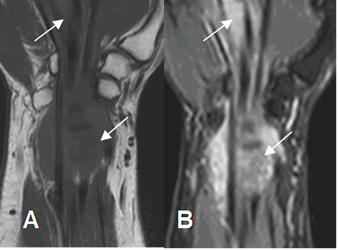

Fig 112 C. Fibromatosis.

A: RM coronal en T1 y B: RM coronal en STIR. Tejido inflamatorio agudo hipointenso en T1

e hiperintenso en STIR, que rodea los tendones flexores, en la muñeca y la palma de la mano.